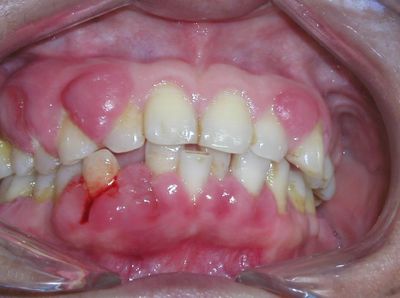

1、轻微的牙龈出血是早期牙龈炎的指征,刷牙时刷毛上有血迹,咬食物时食物上有血迹,说明有牙龈炎。

2、照镜子如果发现有牙龈红肿,一碰就出血的情况,说明可能也有牙龈炎。

3、牙齿有不同程度的松动,牙缝变大,牙根暴露或牙龈红肿、有脓,说明已发展到牙周炎。